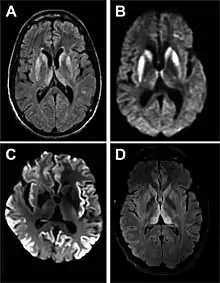

Imaging

Imaging of the brain may be performed during medical evaluation, both to rule out other causes and to obtain supportive evidence for diagnosis. Imaging findings are variable in their appearance, and also variable in sensitivity and specificity.[43] While imaging plays a lesser role in diagnosis of CJD,[44] characteristic findings on brain MRI in some cases may precede onset of clinical manifestations.[45]

Brain MRI is the most useful imaging modality for changes related to CJD. Of the MRI sequences, diffuse-weighted imaging sequences are most sensitive.[46] Characteristic findings are as follows:

• Focal or diffuse diffusion-restriction involving the cerebral cortex and/or basal ganglia. In about 24% of cases DWI shows only cortical hyperintensity; in 68%, cortical and subcortical abnormalities; and in 5%, only subcortical anomalies.[47] The most iconic and striking cortical abnormality has been called "cortical ribboning" or "cortical ribbon sign" due to hyperintensities resembling ribbons appearing in the cortex on MRI.[48] The involvement of the thalamus can be found in sCJD, is even stronger and constant in vCJD.[49]

• Varying degree of symmetric T2 hyperintense signal changes in the basal ganglia (i.e., caudate and putamen), and to a lesser extent globus pallidus and occipital cortex.[44]

Signal hyperintensity in the caudate nucleus and putamen on diffusion-weighted and FLAIR MRI Often presentOften absent

Pulvinar sign-bilateral high signal intensities on axial FLAIR MRI. Also posterior thalamic involvement on sagittal T2 sequencesNot reported Present in >75% of cases